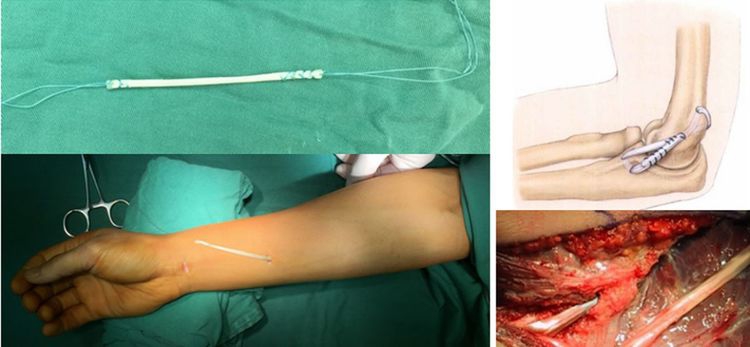

11.尺神经炎

尺神经炎是临床常见的疾病,松解前移是手术治疗的原则,关节镜下通过1个2cm的切口,就能够将尺神经充分松解并前移,切口更小,损伤更小,广受患者欢迎。